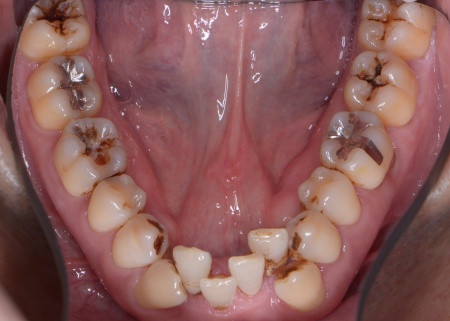

| カウンセリング | 拝見したところ、上下の歯は、ずれたりねじれたりしてデコボコに生えており、著しく歯並びが乱れていました。

またレントゲン撮影をして確認すると、右上前歯は顎の骨の中に埋まっている骨性埋伏(こっせいまいふく)の状態でした。 さらに、左下奥歯は重度の歯周病であり、歯を支えている骨が一部溶けていることが判明しました。 以上のことから、歯並びを整える矯正治療と歯周病の治療を併せて行う必要があると診断しました。 |